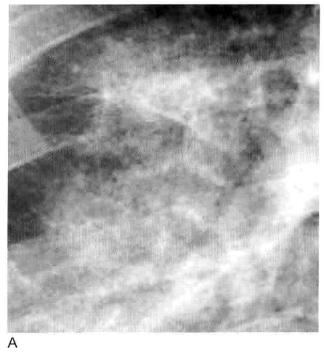

图3 实变:斑片状致密影

A. 肾衰竭引起的肺水肿患者,胸部X线显示肺门周围斑片状实变影;B. CT显示斑片样磨玻璃样实变,其边缘模糊是由于病理进程中肺泡受累程度不同

斑片状肺实变有时在胸部X线片或CT上显示为小叶或多小叶的病变(包括孤立的肺小叶)(图4),可表现为一些小叶密度增高而临近小叶充气正常。